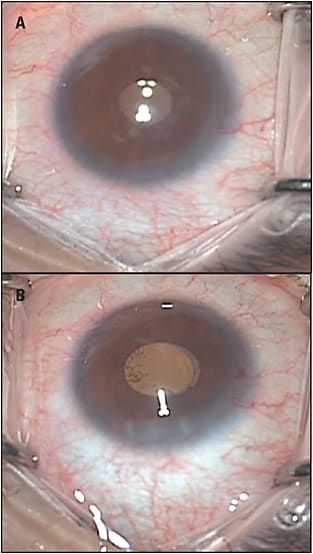

We developed a technique in 2016 called ab-interno canaloplasty (ABiC) and evaluated the safety and efficacy outcomes in 12 patients in whom 1 eye had “traditional” canaloplasty and the other ABiC. Short-term analysis (12 months) showed similar outcomes in IOP and medication reduction between the 2 eyes.12 Unlike canaloplasty, ABiC (viscodilation using the iTrack catheter) comprises all facets of MIGS. It is minimally invasive, conjunctival sparing, performed via an ab-interno approach through clear corneal incisions, blebless, and safe (Figure 2). The microcatheter is introduced into the canal through a very small otomy created in the trabecular meshwork, and microsurgical instruments are used to feed the catheter through the canal. Viscoelastic solution such as Healon GV (Abbott Laboratories) is typically injected into the canal upon withdrawal of the catheter. As the catheter is withdrawn, the surgical technician is instructed to turn or “click” the injector, which forces the viscoelastic through the catheter into the canal and distal collector system, which can be visualized externally by blanching of the episceleral venous system (Figure 3). I typically remove the catheter at a rate of 1 clock hour per second and instruct my technician to click the injector 2 times per clock hour.